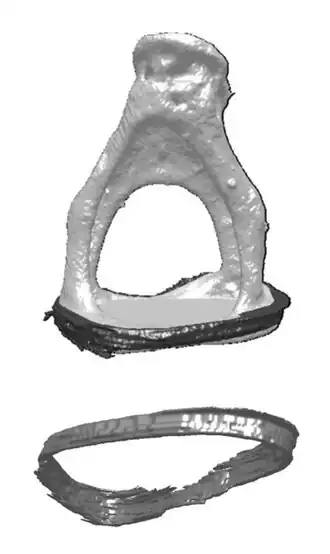

El Ligamento anular del estribo es un anillo de tejido fibroso que conecta la base del estribo a la ventana oval del oído interno.

La calcificación y endurecimiento del ligamento anular del estribo (otosclerosis) es una causa común de sordera en el adulto. Se conoce como ligamento de Rudinger, es laxo y permite a la platina del estribo desplazarse adentro y afuera en la ventana oval.